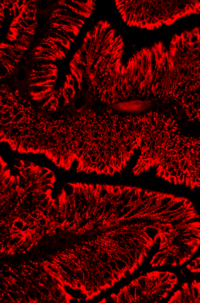

Phase-1-Studie mit Impfstoff VXM01 gegen Dickdarmkrebs Der für die Gefäßneubildung im Tumor wichtige Rezeptor (VEGFR-2) spielt eine entscheidende Rolle bei der Ausbreitung von Dickdarmkrebs. Ein